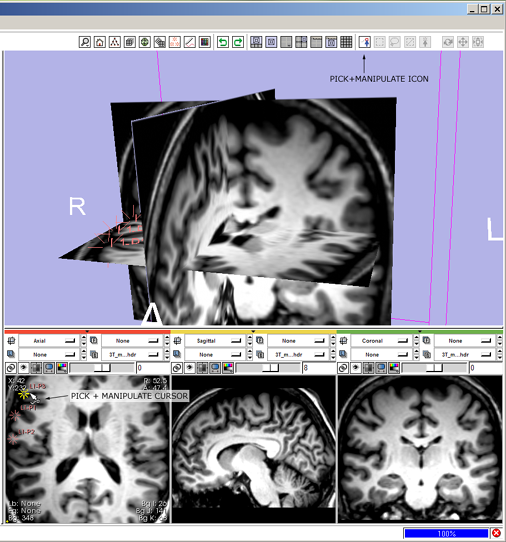

| + | 3(novice) '''track:''' click the view track mouse-mode icon [[image:ToolbarMousePan.png]] | ||

* --> mouse-track icon highlights and all others deselect, cursor changes to indicate mouse-track mode. | * --> mouse-track icon highlights and all others deselect, cursor changes to indicate mouse-track mode. | ||

* then left-Click and drag in the 3D Viewer to translate the view left-right, and up-down, | * then left-Click and drag in the 3D Viewer to translate the view left-right, and up-down, | ||

| − | 3 ''' | + | 3(expert) '''track:''' alt+left-Click and drag in the 3D Viewer, |

| − | + | * --> mouse-track icon [[image:ToolbarMousePan.png]] highlights and all others deselect; cursor changes to indicate mouse-track mode; view tracks. | |

| − | 4 '''place fiducials:''' click the mouse-place icon [[image:ToolbarMousePlace.png]] | + | [[image:SB3.png]] |

3(novice) track: click the view track mouse-mode icon ![]()

- --> mouse-track icon highlights and all others deselect, cursor changes to indicate mouse-track mode.

- then left-Click and drag in the 3D Viewer to translate the view left-right, and up-down,

3(expert) track: alt+left-Click and drag in the 3D Viewer,

- --> mouse-track icon

highlights and all others deselect; cursor changes to indicate mouse-track mode; view tracks.

highlights and all others deselect; cursor changes to indicate mouse-track mode; view tracks.

6(novice) select and move fiducials: click the mouse-pick-and-manipulate icon ![]()

- --> mouse-pick-and-manipulate icon highlights, all others deselect, cursor changes to indicate mouse-pick-and-manipulate mode.

- move mouse to location of fiducial in a Slice Viewer and see the fiducial highlight; left-Click and drag in a Slice Viewer to reposition the fiducial point.

- move the mouse away from the fiducial and see it lowlight.

6(expert) pick-and-manipulate fiducials: press 1-key to switch into mouse-pick-and-manipulate mode.

- --> mouse pick-and-manipulate icon

highlights, and all others deselect; cursor changes to indicate mouse-pick-and-manipulate mode,

highlights, and all others deselect; cursor changes to indicate mouse-pick-and-manipulate mode, - then mouse-over a fiducial point, see it highlight, left-Click and drag to reposition it. Release mouse button and move away, and see the fiducial lowlight.